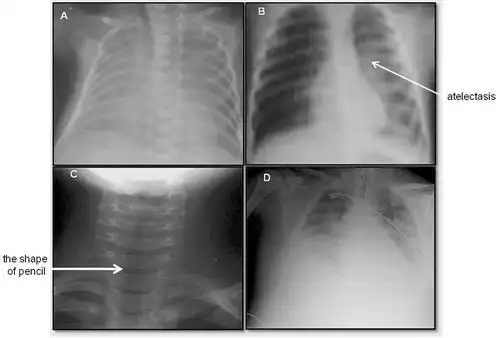

胸片可见两肺弥漫炎性渗出影,因此诊断为小儿支气管肺炎

用了退热贴,就降下来了,第二天去医院,拍的胸片医生说严重支气管肺炎

(详细讲解肺炎胸片和最新病案~)

小儿呼吸道合胞病毒肺炎